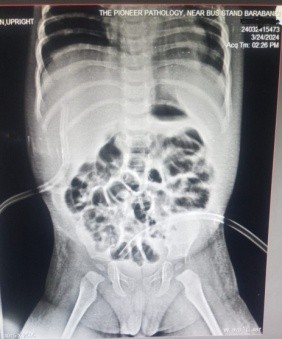

A previously healthy 1-year-old male baby was admitted with clinical signs of severe dehydration after 3 days of diarrhea, vomiting and fever. Upon admission he was lethargic and had clinical signs of shock with cold extremities, a prolonged capillary refill time (>3s) and tachycardia and abdominal distention. He was managed conservatively and advised X ray abdomen supine [Figure 1] which showed post diarrhoeal paralytic ileus with dilated bowel loops. Ultrasonography showed only mild fluid collection with internal septations. A plain abdominal x ray (erect) revealed free sub-diaphragmatic air [figure 2]. Suspecting intestinal perforation we decided to perform an exploratory laparotomy which revealed a small post-pyloric duodenal perforation [Figure 4]. Grahams patch repair was performed [Figure 5]. The postoperative course was uneventful [Figure 3]. Rotavirus antigen was found in feces.

Figure 3 : X Ray Abdomen Erect Done Post Operatively Normal X ray Abdomen With Drains In Situ

Figure 3